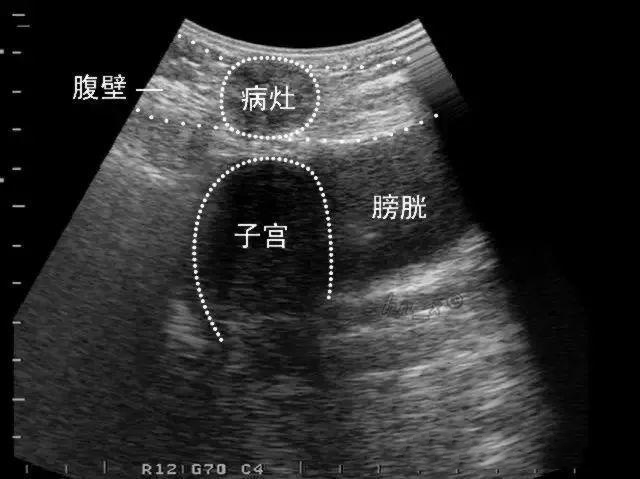

4.子宫镜和腹腔镜检查:最佳时间月经干净后3-7天适合子宫镜或者腹腔镜检查,因为子宫镜检查必须灌水撑开子宫腔以利检查,腹腔镜是将显影剂注入子宫腔及输卵管,来判读输卵管是否堵塞。